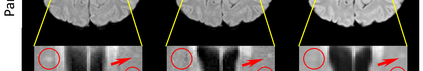

Multiple Sclerosis (MS) is a chronic progressive neurological disease characterized by the development of lesions in the white matter of the brain. T2-fluid-attenuated inversion recovery (FLAIR) brain magnetic resonance imaging (MRI) provides superior visualization and characterization of MS lesions, relative to other MRI modalities. Longitudinal brain FLAIR MRI in MS, involving repetitively imaging a patient over time, provides helpful information for clinicians towards monitoring disease progression. Predicting future whole brain MRI examinations with variable time lag has only been attempted in limited applications, such as healthy aging and structural degeneration in Alzheimer's Disease. In this article, we present novel modifications to deep learning architectures for MS FLAIR image synthesis, in order to support prediction of longitudinal images in a flexible continuous way. This is achieved with learned transposed convolutions, which support modelling time as a spatially distributed array with variable temporal properties at different spatial locations. Thus, this approach can theoretically model spatially-specific time-dependent brain development, supporting the modelling of more rapid growth at appropriate physical locations, such as the site of an MS brain lesion. This approach also supports the clinician user to define how far into the future a predicted examination should target. Accurate prediction of future rounds of imaging can inform clinicians of potentially poor patient outcomes, which may be able to contribute to earlier treatment and better prognoses. Four distinct deep learning architectures have been developed. The ISBI2015 longitudinal MS dataset was used to validate and compare our proposed approaches. Results demonstrate that a modified ACGAN achieves the best performance and reduces variability in model accuracy.